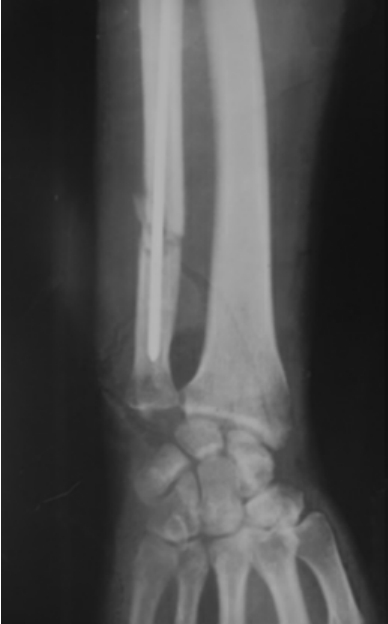

如图7-4-4至图7-4-6即为骨折的影像学检查X线片。

图7-4-4 尺骨骨折当日

图7-4-5 内固定术后

图7-4-6 骨折术后3个月